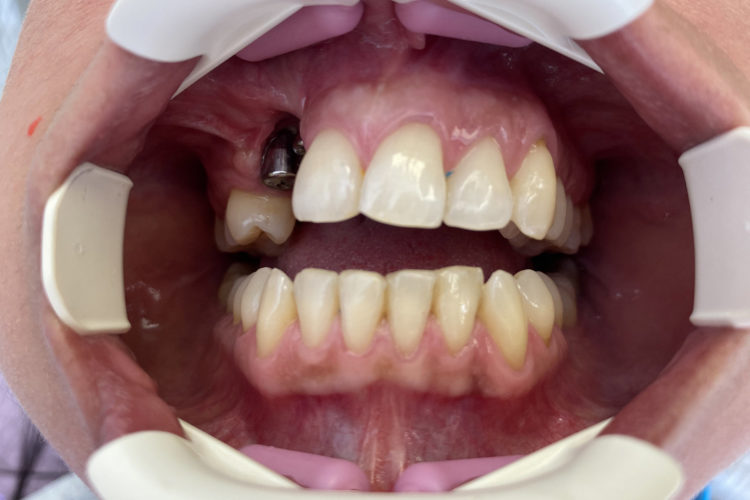

Pacienta in varsta de 39 de ani, a venit in clinica cu pierdere osoasa majora la maxilar in urma unei extractii de canin inclus si pierderea dintelui invecinat. Dupa o interventie de aditie osoasa, pacienta a primit  2 implante DENTIUM pe care s-a efectuat o protezare fizionomica fixa (baza titan plus suprastructura insurubata de zirconiu), cu refacerea conturului gingival si restaurarea functionala a arcadei. Pacientei i s-a propus si redresarea ortodontica pe care a amanat-o pentru o data ulterioara.